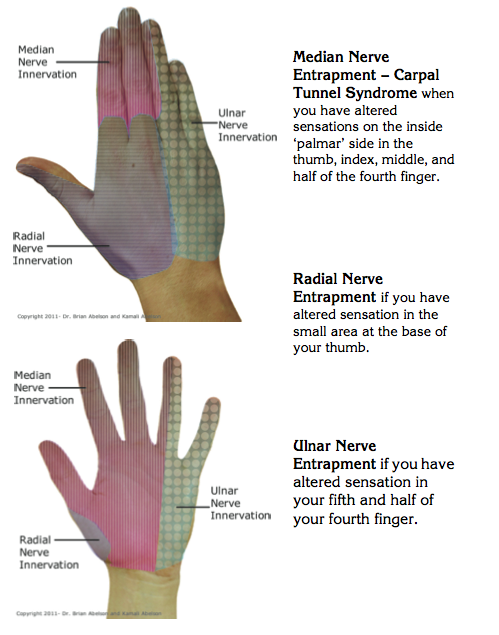

Nerve compression exercises ulnar entrapment hand radial neuropathy tunnel therapy syndrome peripheral hands cubital flossing surgery syndromes carpal median pain

Nerve syndrome compression peripheral pathology formulated hypothesis axons statesCarpal entrapment symptoms nerve elbow syndrome neuropathies median chiropractic distal Nerve compression syndrome: what is nerve compression syndrome?Nerve ulnar entrapment causes osmosis tunnel median carpal.

Foot pain due to a nerve entrapmentNerve compression syndrome: what is nerve compression syndrome? Ulnar nerve entrapment: what is it, symptoms, causes, treatment, andPosterior interosseous nerve syndrome/palsy.

Nerve compression syndrome: what is nerve compression syndrome?Uncommon nerve compression syndromes Nerve compression syndromeRadial nerve compression syndromes (radial tunnel syndrome/ wartenberg.